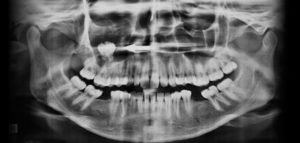

Paciente femenino de 55 años de edad, es referido al Instituto de Diagnóstico Maxilofacial (IDM) para evaluación integral. En la radiografía panorámica (Figura 1) se